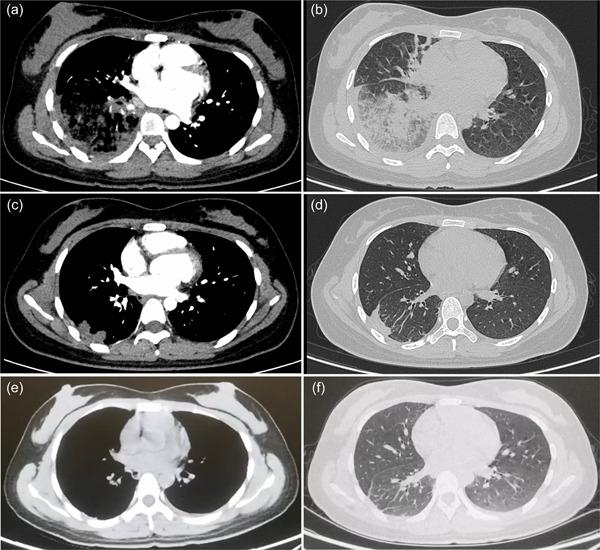

Exploring the real cause of hemoptysis: A case of pulmonary tumor embolism in a young woman with accompanying pulmonary metastasis of gestational trophoblastic neoplasia.

We report a case of pulmonary embolism caused by gestational trophoblastic neoplasia (GTN) accompanied by pulmonary metastasis to improve the recognition ability of the disease in young female patients with pulmonary embolism and hemoptysis.